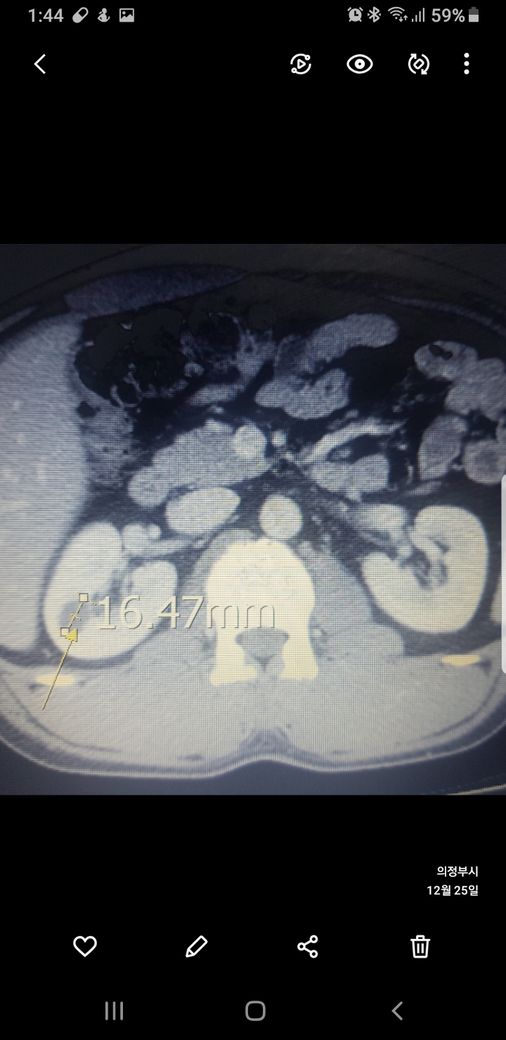

복부ct 작년 11월 , 올해 12월 촬영분입니다.

우측신장에 작년에는 1.7cm 물혹이 올해는 같은곳에 1.2cm 출혈성낭종이라는데

사진 1~4번째 는 작년

둘다 같은 병변이고 비조영증강에서 약간의 고음영 소견이 있어 출혈성 낭종이 의심됩니다.

신장의 낭성병변의 분류에서 1, 2, 2F, 3, 4이렇게 나뉘는데, 2에 해당되는 소견입니다.